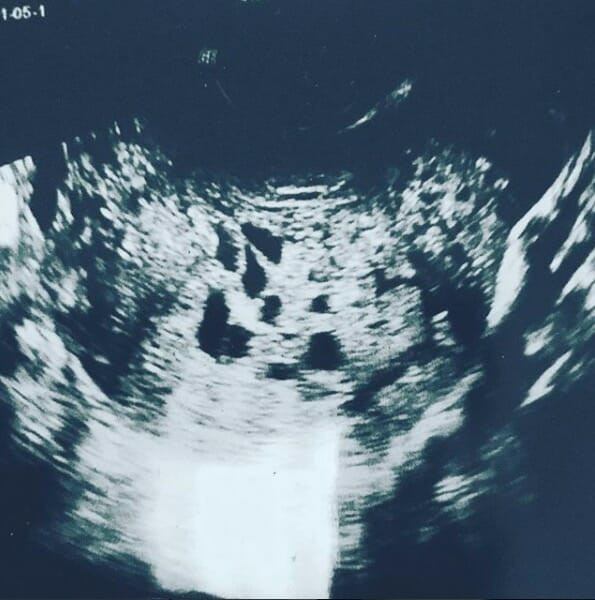

İkinci kez anne olacağını öğrenen Lauren Knowles sevinçten havaya uçtu. Eşi Trent ile beraber geniş bir aileye sahip olmak istiyorlardı. Doktor yedi aylık hamile olduğunu söyledi. The Daily Mail’den aktarılanlara göre 27 yaşındaki İskoç anne Lauren Knowles sıradışı bir şey tecrübe etmiş. Hamile olduğunu öğrenen kadın önce çok sevindi. Yedinci haftadan sonra ise kötü hissetmeye başladı. Lauren, Daily Mail’e “Birden kanama oluştu” dedi. Kadın derhal hastaneye götürüldü. Burada korkunç gerçeği öğrendi.

Doktorların söylediğine göre Lauren molar gebelikle karşı karşıyaymış. Yumurtanın döllenmesindeki bazı hatalar sonucu rahim içinde cansız bir organizma oluşmasına molar gebelik veya mol hidatiform adı veriliyor. Molar gebelikte, normalde plasenta oluşması gerekirken kist oluşuyor. En kötüsü de kist kötü huylu oluyor.

Lauren, “Ben karnımda bebeğimin büyüdüğünü zannederken meğerse tümör büyüyormuş” dedi. Büyümeye devam etti. Cerrahlar, kanserleri hücreleri almayı başardılar. Lauren ise kemoterapi tedavisi görmeye başladı ve saçları döküldü. Maalesef tümörü büyümeye devam etti. Bir gün Lauren şiddetli karın ağrısı sonucu tümörünü tuvalette ‘dünyaya getirdi’.